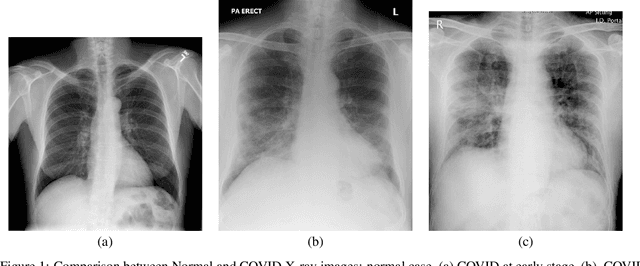

Abstract:Future SARS-CoV-2 virus outbreak COVID-XX might possibly occur during the next years. However the pathology in humans is so recent that many clinical aspects, like early detection of complications, side effects after recovery or early screening, are currently unknown. In spite of the number of cases of COVID-19, its rapid spread putting many sanitary systems in the edge of collapse has hindered proper collection and analysis of the data related to COVID-19 clinical aspects. We describe an interdisciplinary initiative that integrates clinical research, with image diagnostics and the use of new technologies such as artificial intelligence and radiomics with the aim of clarifying some of SARS-CoV-2 open questions. The whole initiative addresses 3 main points: 1) collection of standardize data including images, clinical data and analytics; 2) COVID-19 screening for its early diagnosis at primary care centers; 3) define radiomic signatures of COVID-19 evolution and associated pathologies for the early treatment of complications. In particular, in this paper we present a general overview of the project, the experimental design and first results of X-ray COVID-19 detection using a classic approach based on HoG and feature selection. Our experiments include a comparison to some recent methods for COVID-19 screening in X-Ray and an exploratory analysis of the feasibility of X-Ray COVID-19 screening. Results show that classic approaches can outperform deep-learning methods in this experimental setting, indicate the feasibility of early COVID-19 screening and that non-COVID infiltration is the group of patients most similar to COVID-19 in terms of radiological description of X-ray. Therefore, an efficient COVID-19 screening should be complemented with other clinical data to better discriminate these cases.